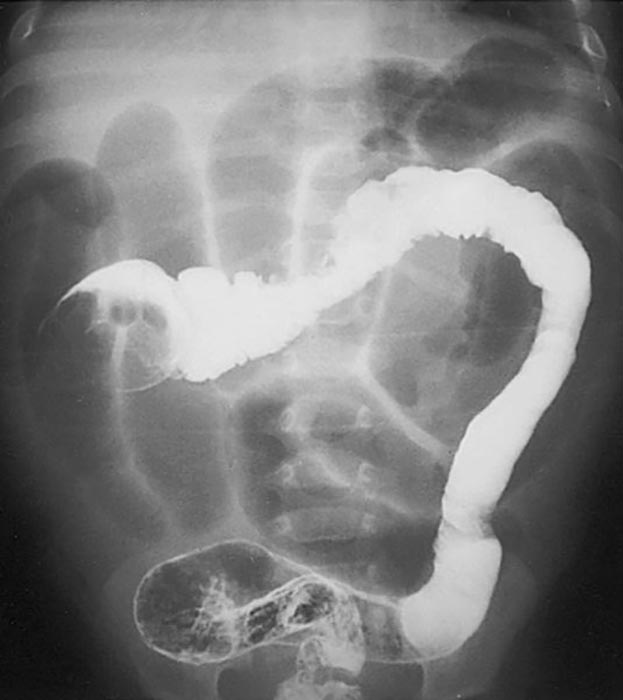

What is volvulus? (twist)

A twisting of a portion of the bowel that may cause obstruction and compromise blood supply.

Where does volvulus most commonly occur?

In the cecum and sigmoid colon. (image shows cecal volvulvus)

How does sigmoid volvulus occur?

The sigmoid twists on its mesenteric axis, rotating left or right.

What are common symptoms of volvulus?

Severe abdominal pain, vomiting, and abdominal distension.